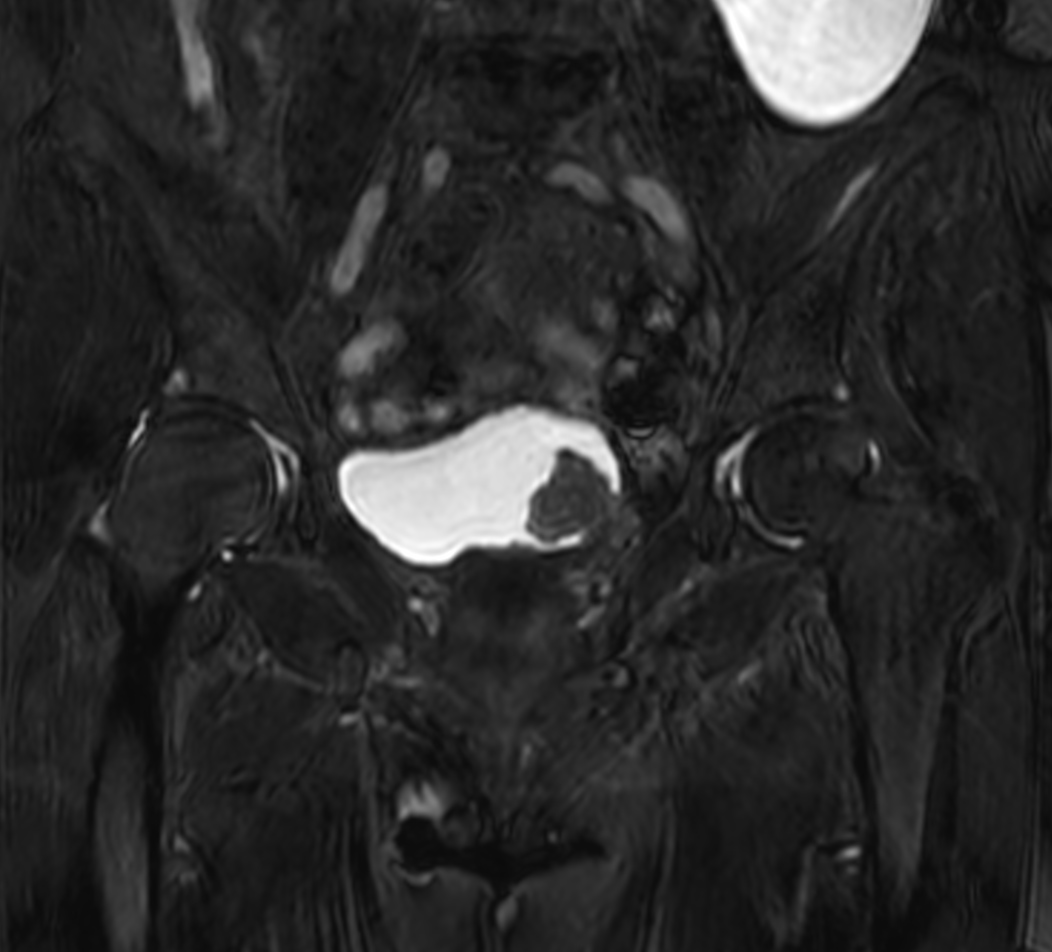

Patient with bladder cancer. The ExamCard includes techniques for motion reduced imaging (MultiVane XD), 3D TSE imaging (PelvisVIEW) allowing for multiple image directions in one single scan, a multi-phase contrast-enhanced sequence (4D FreeBreathing) to improve imaging confidence and Compressed SENSE to accelerate the entire exam.

T2w TSE MultiVane XD